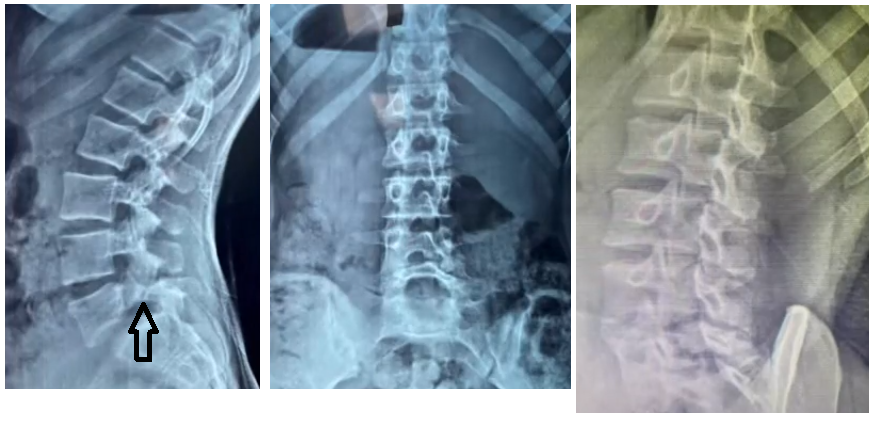

• Quais as principais incidências radiográficas para avaliação da espondilolistese ístimica?

A

• AP + Perfil (em pé)

• Oblíqua (mostra o cachorro de Lachapelle)

• Ap de Fergunson

• Na avaliação radiográfica em AP, o que representa o sinal de napoleão invertido?

• Grau 5 de Meyerding → escorregamento completo de L5